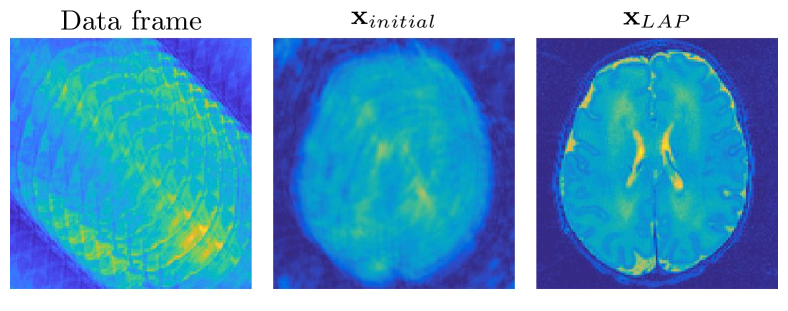

For an initial guess for the motion parameters, we start with (corresponding to a relative error of %). Using this initialization, we solve a linear least-squares problem to get an initial guess for the image. For % added Gaussian noise in the data, the initial guess for the image has a relative error of around %. We show the initial guess in Fig. 5.

LAP, VarPro, and BCD provide fairly accurate reconstructions of both the image and motion parameters for quite large values of noise using either HyBR or the identity as a regularizer; see Figs. 5 and 6. This is likely due to the fact that the problem is not severely ill-posed and is highly over-determined (32 sensor readings for each point in Fourier space.) For this example, the hybrid regularization approach for LAP and BCD produces the best results, with LAP requiring considerably fewer iterations. We remark that the best regularization from this problem differs from the super-resolution problems, which shows the importance of the flexibility that LAP offers for regularizing the image. The comparative speed of LAP is observable for the relative error plots for the problem with % noise and further evidenced in Table 3 for all noise levels over separate realizations of the problem. For the gradient-based regularizer, all three methods do not recover the motion parameters accurately. We also note that the number of iterations and their cost is an important consideration for this problem. Because of the distance of the initial guess from the solution, this problem requires more iterations than the super-resolution examples. Additionally, the high number of 2D FFTs required for a single matrix-vector multiplication makes multiplications by the Jacobian and expensive. Table 3 shows that LAP outperforms VarPro and BCD for both choices of regularizer by requiring fewer, cheaper iterations in terms of both time and matrix-vector multiplications. The difference in cost is most dramatic when compared with VarPro again due to the large number of FFTs required for a single matrix-vector multiplication and the large number of such multiplications required within each VarPro function call. For BCD and LAP, the number of matrix-vector multiplications is similar, but BCD requires more iterations for convergence. Overall, we see that LAP is a better choice for this problem and that it provides better reconstructions of both the image and motion in fewer, cheaper iterations.